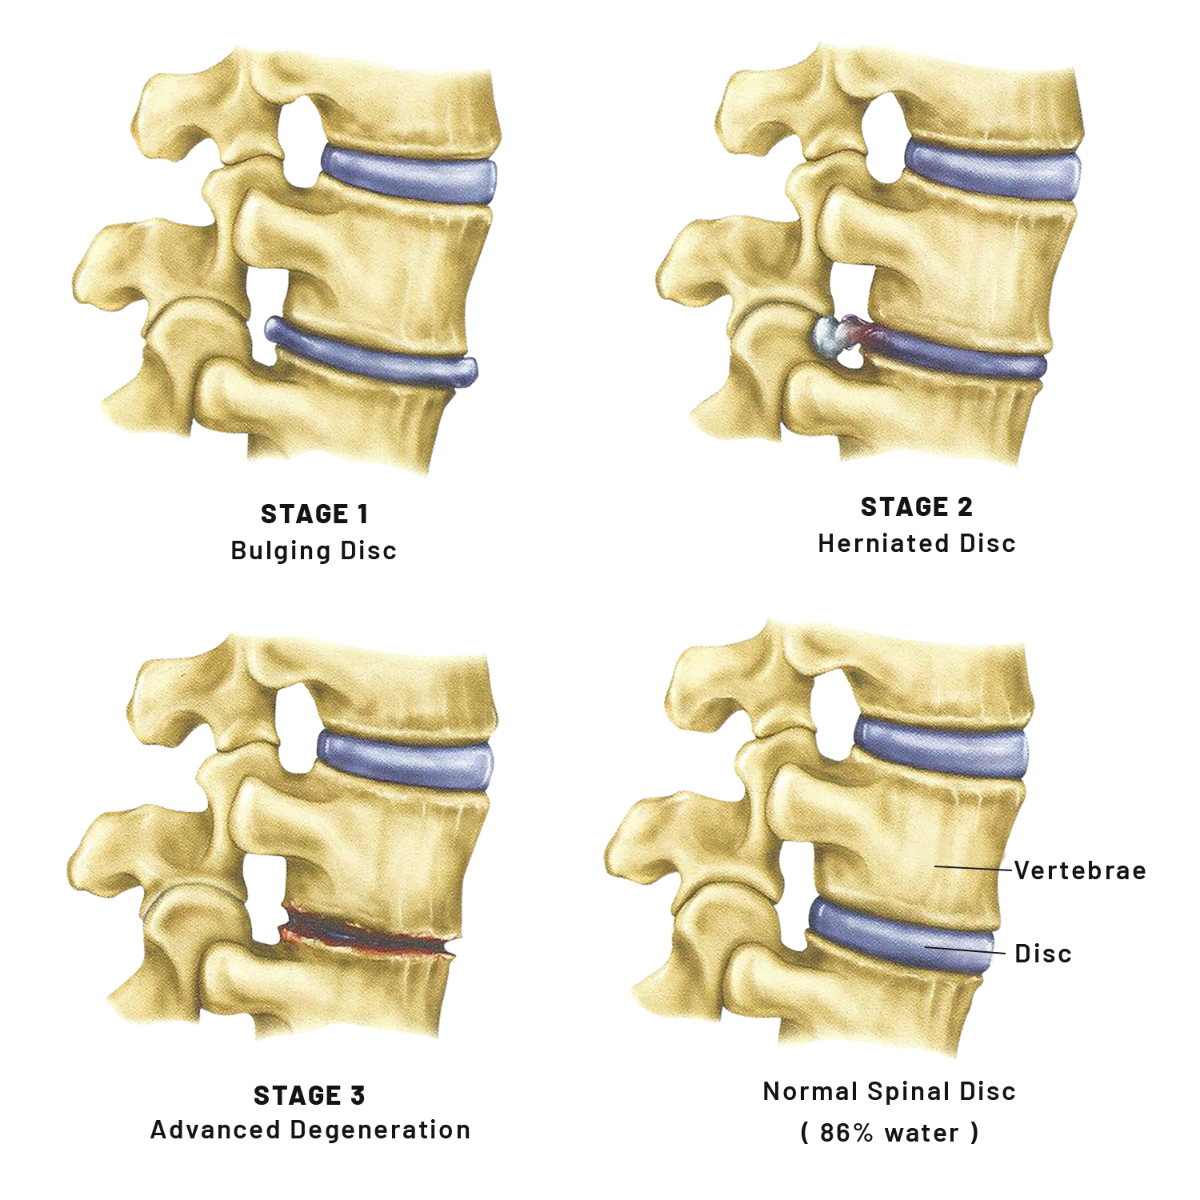

The disc is designed to provide a cushion between the bones of the spine. The function of the disc is to absorb shock and to protect the nerve in the spine. If the disc slips, bulges or degenerates, the result is pressure on the nerve and pain.

Spinal Disc Disorders